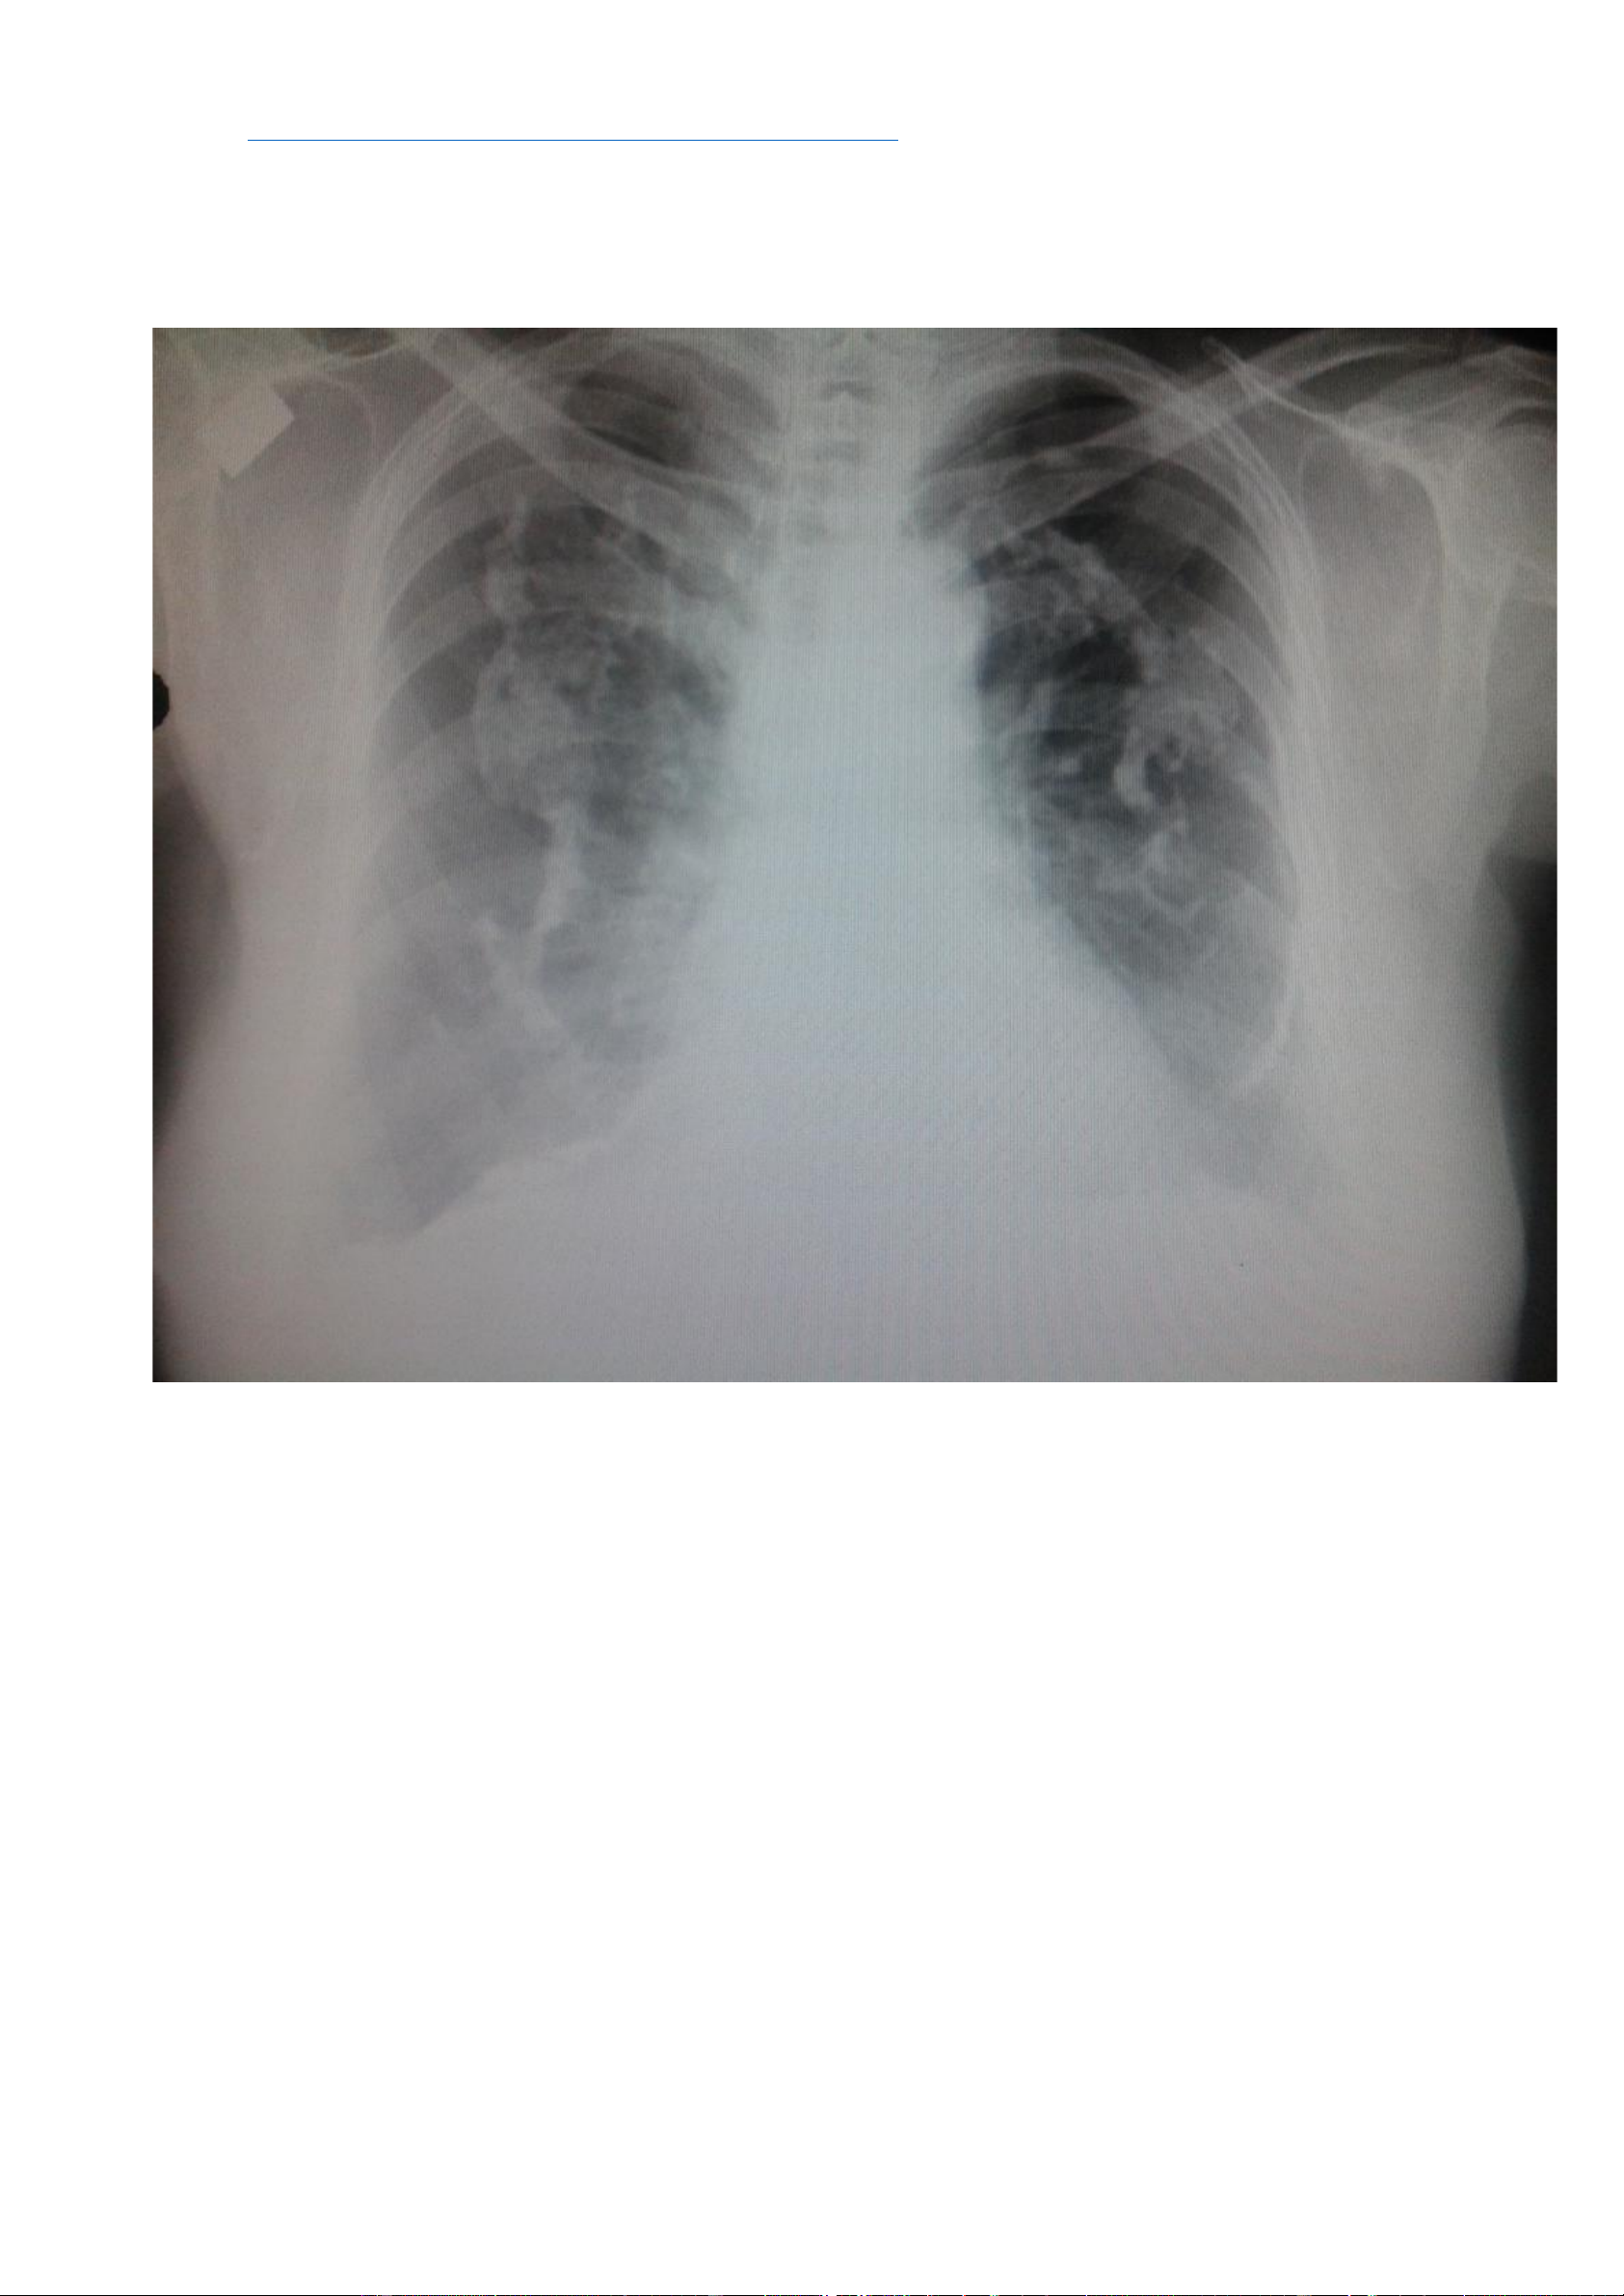

Nguồ https://radiopaedia.org/cases/asbestos-related-pleural-plaques-2 -

nh nhân: Bệnh nhân nam, 75 tuổi, tiền sử phơi nhiễm với amiăng. - Hình ả lOMoAR cPSD| 22014077 Phan Tùng Bách

Các mảng màng phổi vôi hoá hai bên. - Hình ảnh CT: + Cửa sổ nhu mô: lOMoAR cPSD| 22014077 Phan Tùng Bách